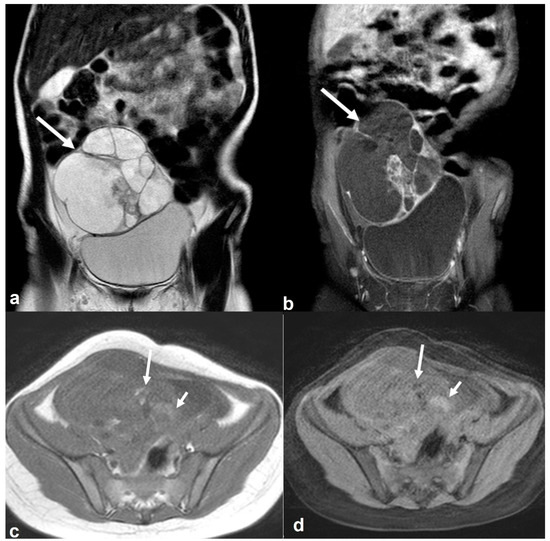

2.6.1. Mucinous Rectosigmoid Cancer

2.6.2. Appendiceal Mucocele—PMP

2.6.3. Liposarcoma/Schwannoma